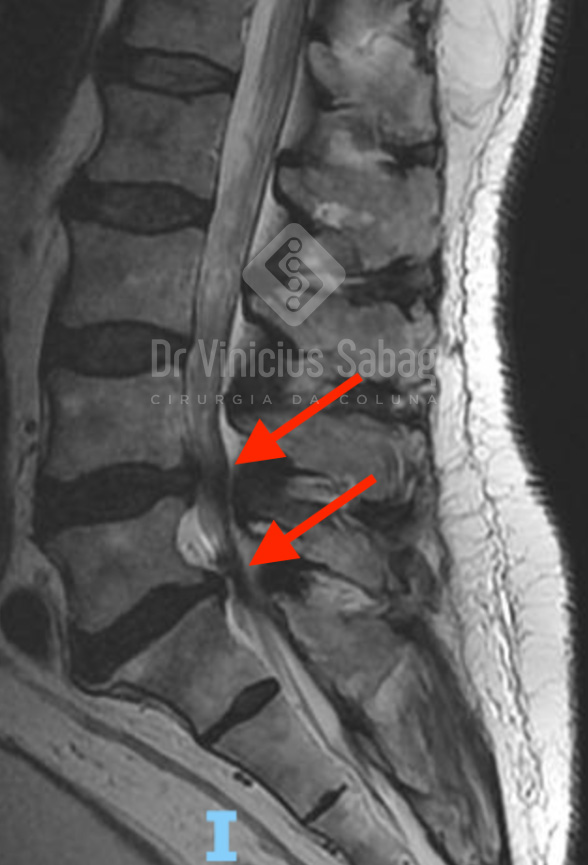

Foi realizada ressonância magnética da coluna lombar, que evidenciou estenose de canal lombar nos níveis L4-L5 e L5-S1, compatível com o quadro clínico apresentado.

Ressonância magnética evidenciando estenose do canal lombar nos níveis L4-5 e L5-S1 (setas vermelhas).